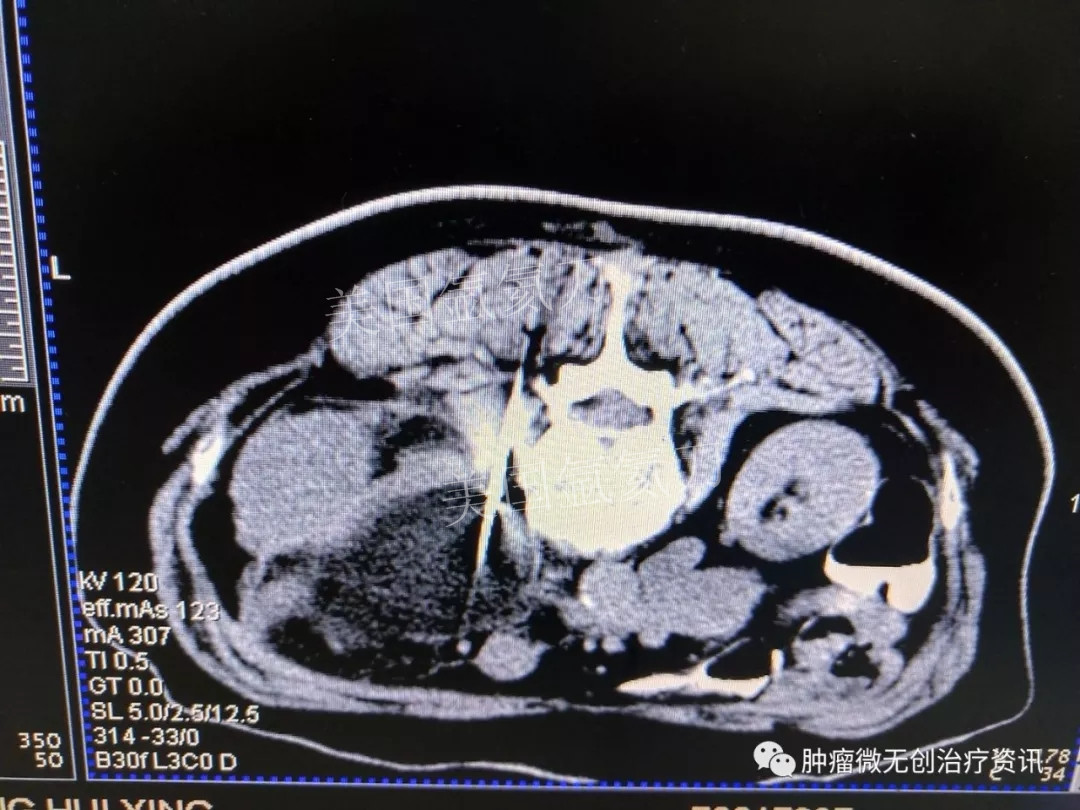

腹膜后脂肪肉瘤氩氦刀冷冻消融治疗——中国人民解放军第307医院

66岁女性患者,因腹膜后脂肪肉瘤,入住于中国人民解放军第307医院肿瘤微创治疗科。结合患者情况,行氩氦刀冷冻消融治疗。